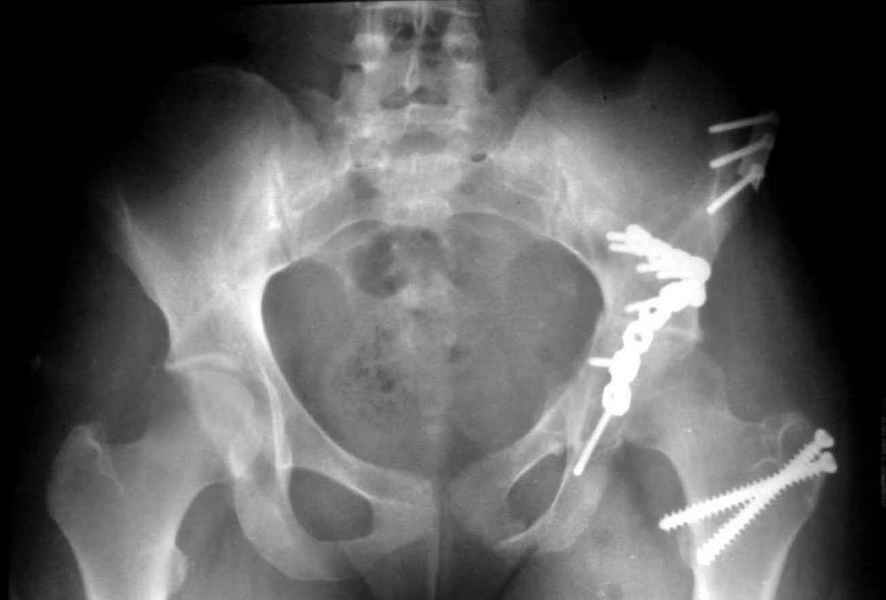

Посылаю схемы и 3D реконструкцию подобного повреждения. Называется он полным высоким двухколонным переломом вертлужной впадины, а "переломы крыла и тела подвздошной кости" входят в это понятие.

Вариантов остеосинтеза много (можно и не оперировть, т.к. конгруентность при таких переломах как правило сохраняется)

1 закрытая репозиция аппаратом + фиксация через проколы винтами

2 закрытая репозиция передней колонны + открытая задней колонны из задне-неружного доступа

3 открытая репозиция передней колонны из подвздошнго доступа + открытая задней колонны из задне-наружного доступа

4 открытая репозиция из илиоингвинального доступа

5 открытая репозиция из Y образного доступа

Я бы ориентировался на Y образный доступ

или из двух если есть сомнения в целостности задних отделов крыла.

прикладываю схему доступа и случай.

Одним задне наружным переднюю колонну не достать, а илио-ингвинальный более сложный не позволяет контролировать суставную поверхность и трудно управлять задней колонной.